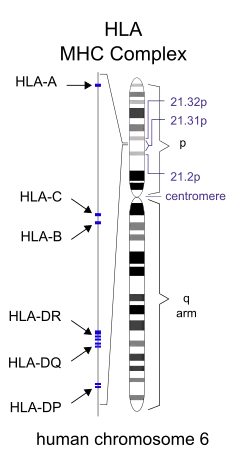

Foruden familieundersøgelser er specifikke gener blevet sat i forbindelse med MS. Forskelle i det humane leukocytantigen (HLA)-system – en gruppe gener i kromosom 6, der tjener som major histocompatibility complex (MHC) i mennesker – øger sandsynligheden for at lide af MS.[1] Det mest konsekvente resultat er sammenhængen mellem MS og alleler af MHC defineret som DR15 og DQ6.[1] Andre loci har vist en beskyttende effekt, heriblandt C554 og DRB1*11.[1]